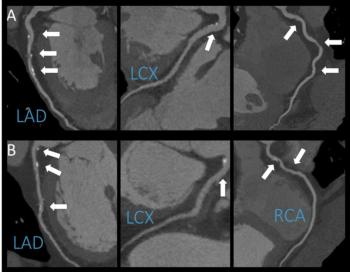

"CCTA is an excellent diagnostic modality to noninvasively depict the coronary wall and identify atherosclerotic lesions," said study author Júlia Karády, M.D., from the MTA-SE Cardiovascular Imaging Research Group, Heart and Vascular Center at Semmelweis University in Budapest, Hungary. "Furthermore, we're able to characterize plaques and differentiate between several types. Prior studies used cardiovascular risk factors—like high cholesterol levels—and cardiovascular outcomes to study the effects of alcohol, but our study is unique in that we analyzed both drinkers and non-drinkers using CCTA, which may shed some light on how alcohol may or may not contribute to the development of fatty plaques in the arteries of the heart."

Images (JPG, TIF):